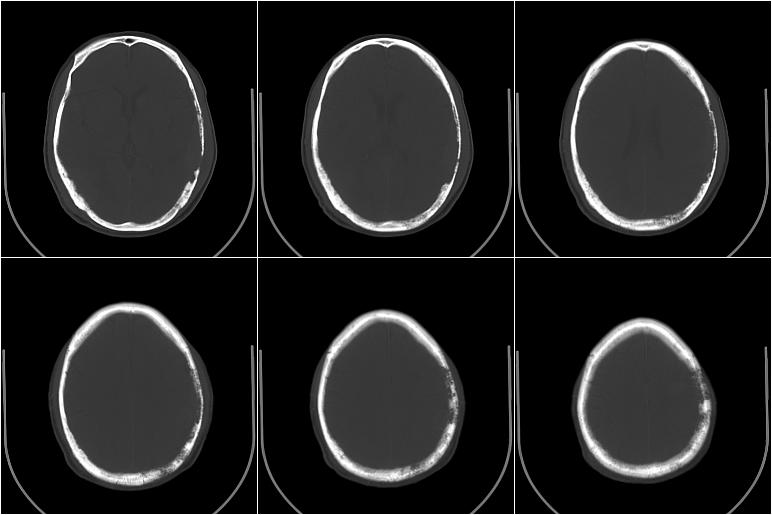

以下是引用边生丽在2009-8-17 11:43:00的发言:[br][br] [br] 右肺中心型癌伴右肺下叶不张、双肺转移并癌性淋巴管炎、心包和双侧胸腔积淮(转移?)、脑转移、肝转移、多骨(颅骨、椎骨)转移。 [br] [br]

以下是引用随光逐影在2009-8-17 14:09:00的发言:[br]支持 右肺中央型癌伴右肺下叶肺不张,纵隔淋巴结转移,双肺转移并癌性淋巴管炎,心包和双侧胸腔积液,脑转移、肝转移、多发性骨(颅骨、脊椎)转移。